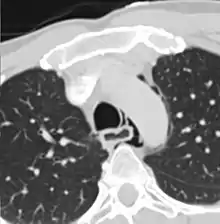

| Axial CT image through the upper chest showing extraluminal air (Pneumomediastinum) surrounding the trachea and esophagus | |

The diagnosis of Boerhaave's syndrome is suggested on the plain chest radiography and confirmed by chest CT scan. The initial plain chest radiograph is almost always abnormal in patients with Boerhaave's syndrome and usually reveals mediastinal or free peritoneal air as the initial radiologic manifestation. With cervical esophageal perforations, plain films of the neck show air in the soft tissues of the prevertebral space.

Hours to days later, pleural effusion(s) with or without pneumothorax, widened mediastinum, and subcutaneous emphysema is typically seen. CT scan may show esophageal wall edema and thickening, extraesophageal air, periesophageal fluid with or without gas bubbles, mediastinal widening, and air and fluid in the pleural spaces, retroperitoneum or lesser sac.